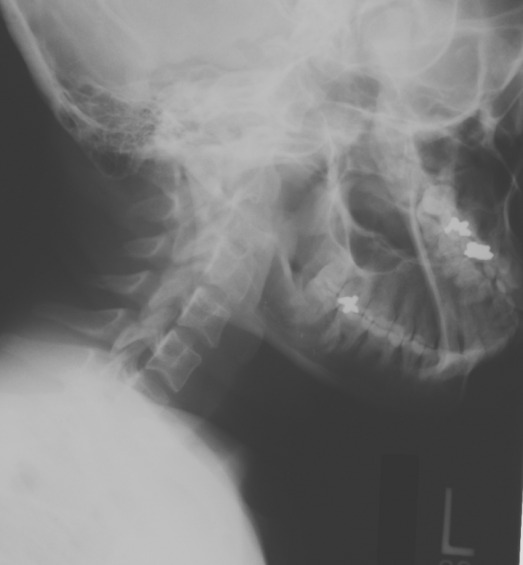

The main finding is of rotational and left lateral flexion of the upper cervical spine. This postural change and the history of MVA is indicative of acute torticollis.

The characteristic clinical findings are often sufficient to diagnose torticollis, however x-rays may be performed. In cases such as the one presented here where there is a history of acute trauma producing a torticollis, the neck should be immobilized until CT or MRI is performed to further exclude the possibility of a cervical spine fracture, dislocation, or epidural hematoma. If the patient is experiencing pins and needles sensations, weakness, or numbness in the arms and/or legs, difficulty walking, difficulty with speech, or difficulty breathing then CT/MRI must be performed to exclude a potential neoplasm, infection, or other predisposing condition.